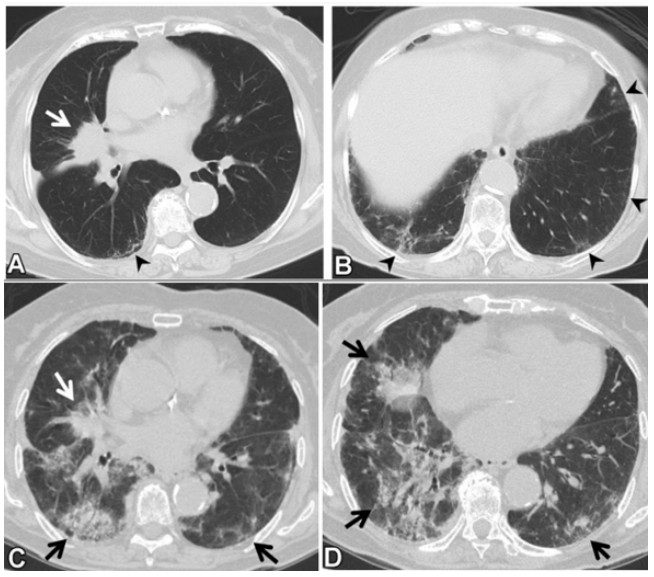

(1)感染性疾病:病毒性?细菌性?真菌?非典型病原体?吸入性肺炎?(2)非感染性疾病:心衰?急性肺栓塞?自身免疫性疾病?麻醉/手术相关肺损伤?急性间质性肺炎?回顾分析患者入院时胸部CT: 双肺靠近外周近胸膜处有轻微细小间质样改变(图4)。诊断:急性间质性肺炎;Ⅰ型呼吸衰竭;左肺下叶部分切除术后;高血压病。ECMO支持;呼吸机支持;甲泼尼松80 mg q12h,尼达尼布;镇静镇痛;抗感染;营养支持。ECMO第6天, 术后第18天, 肺部病变进一步加重(图5)。血气分析: pH 7.543, PaO2 154 mmHg, PaCO2 33.2 mmHg(ECMO, FiO2 100%, MV FiO2 60%)。术后第26天复查胸部CT未见改善。患者最终死亡。笔者团队也曾接诊过一例早期肺癌患者,2013年和2014年随访肺部结节均无明显变化。2015年胸部手术后2天,两肺变白(图6)。当时医生警惕性非常高,立刻行胸部CT检查并予相应治疗,患者最终存活。2022年RadioGraphics 杂志报道一例85岁女性腺癌患者奥希替尼治疗5个月后。图7-A和B为治疗前胸部CT图像,可见右肺中叶有肿块(A中箭头)。胸膜下区域磨玻璃改变和网状结构(箭头)提示存在间质性肺异常(Interstitial Lung Abnormalities,ILA)。治疗5个月后的轴位CT图像显示肿块(C中白色箭头)、弥漫性磨玻璃改变和合并症(黑色箭头)。图源:Radiographics, 2022, 42(7):1925-1939.另一例66岁右上肺鳞癌患者,术前CT显示肿块(图8-A中箭头)位于肺右上叶。轻度磨玻璃改变(箭头),提示ILA,见于胸膜下区域。图8-C和D为术后CT,显示弥漫性磨玻璃样改变和实变(箭头),牵引性支气管扩张症(图8-C中箭头),也可见胸腔积液(图8-D中箭头)。图源:Radiographics, 2022, 42(7):1925-1939.